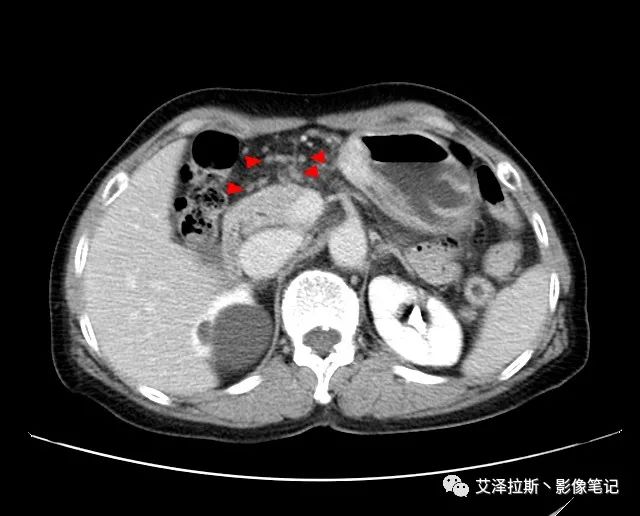

圖2 腫瘤

【影像所見】 胃竇部狹窄,胃壁環形增厚,小彎側見一巨大潰瘍,周圍伴“環堤征”,漿膜面不完整,胃周脂肪見網格狀條索影,病灶與肝臟左葉、胰腺鉤突脂肪間隙消失,增強掃描病灶明顯強化。引流區內約15個區域淋巴結受累。

【診斷意見】 胃竇部胃癌(T4N3期) 該病例腫塊突破漿膜層,與肝臟左葉、胰腺鉤突分界不清,脂肪界面消失,定為T4期; 受累及的淋巴結為15個區域,定為N3; 有無遠處轉移尚不明確,所以M期暫時無法確定。